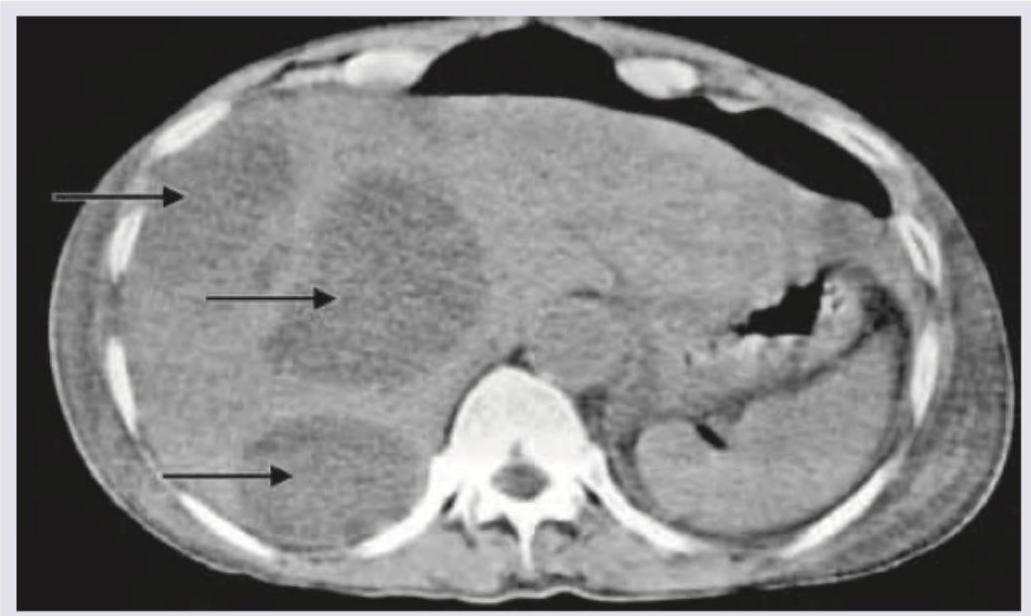

Explanation: ***Hydatid cyst*** - The image shows a large, **multiloculated cystic lesion** within the liver, typical of a hydatid cyst with **daughter cysts** (indicated by arrows). - The presence of **internal septations** and **daughter cysts** strongly suggests **Echinococcus granulosus infection**. - Classic imaging features include the "**water lily sign**" (floating membranes) and **wheel-spoke pattern** of septations. *Liver abscess* - A liver abscess typically appears as a **single or multiple fluid-filled cavities** with **rim enhancement** on contrast CT. - Usually associated with **fever, leukocytosis**, and may show **gas bubbles** if pyogenic. - Lacks the characteristic **daughter cyst** appearance and organized septations seen in hydatid disease. *Hepatic adenoma* - Hepatic adenomas are **solid, well-circumscribed lesions** that may contain **fat** and show **arterial phase enhancement**. - They can undergo **hemorrhage** but do not present as **multiloculated cysts** with daughter cysts. - Typically occur in women on **oral contraceptives**. *Hepatocellular carcinoma* - HCC is typically a **solid mass** with characteristic **arterial phase hyperenhancement** and **venous/delayed phase washout**. - May show **capsule appearance** and can invade vessels. - While large HCCs can have **necrotic areas**, they lack the classic "**daughter cyst**" appearance pathognomonic of hydatid disease.